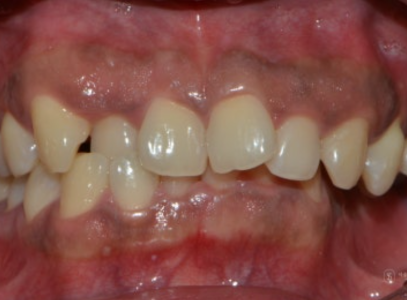

이 환자분은 얼굴 자체의 비대칭도 어느 정도 있었지만, 그보다 치열의 비대칭이 상당히 심한 경우였습니다.

정면에서 입 안을 보면 위아래 치열의 중심선이 맞지 않고, 왼쪽 위 어금니가 전반적으로 아래로 처져 있는 반면, 왼쪽 아래 어금니는 거의 보이지 않을 정도였습니다.

왼쪽 측면 사진에서는 아래 어금니가 위 어금니에 완전히 가려지는 가위교합(위 어금니가 아래 어금니에 비해 바깥쪽에 있어

가위처럼 엇갈려 물리는 상태)이 관찰되었습니다.

교합면(위에서 내려다본 모습)을 보면, 치아 배열이 불규칙할 뿐 아니라

위·아래 치열 모두에서 특히 왼쪽 치열이 심하게 좁아지고 찌그러져 있는 상태임을 확인할 수 있었습니다.